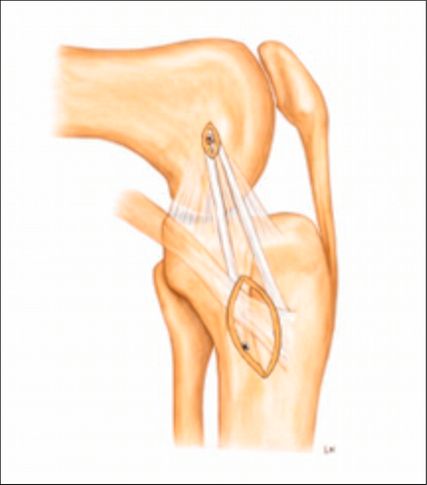

Anteromediale Tenodese

Die anteromediale Tenodese unter Verwendung der gestielten Gracilis- oder Semitendinosus-Sehne dient der Augmentation bzw. Rekonstruktion sowohl des tiefen als auch des oberflächlichen medialen Kollateralbandes (d/sMCL) über zwei funktionelle Bündel. Abhängig vom zugrunde liegenden Verletzungsmuster kann der Eingriff über einen minimalinvasiven oder einen offenen Zugang durchgeführt werden. Die Technik eignet sich bei akuten Eingriffen in Kombination mit einer MCL-Naht bzw. Refixation im Sinne eines „Bio-Brace“. Darüber hinaus kann sie bei chronischen Fällen mit leichter bis moderater anteromedialer Instabilität mit oder ohne VKB-Rekonstruktion durchgeführt werden. Der Ablauf eines solchen Eingriffes ist wie folgt: Die Sehne wird proximal mittels offenen Sehnenstrippers entnommen, während die tibiale Insertion erhalten bleibt. Die femorale Fixation der gedoppelten Sehne erfolgt im hinteren Anteil des nativen Ansatzes des oberflächlichen Längsbandes, während das freie Sehnenende im Zentrum der distalen tibialen Insertionsstelle des oberflächlichen medialen Kollateralbandes fixiert wird. Eine detaillierte Beschreibung der Operationstechnik ist über den QR-Code (Abb. 2,3) als Videoanleitung abrufbar.1